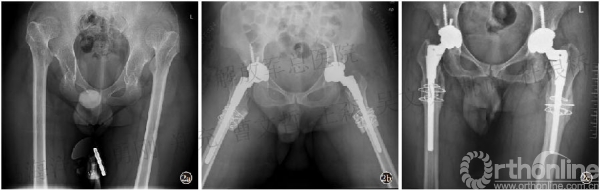

采用SSTO复位:截除股骨头后,进行股骨远端及近端髓腔磨锉,植入S-ROM柄试模。牵引下测量股骨头旋转中心与髋臼中心的距离,紧贴小粗隆下方横行截骨,截骨长度为所测距离减1.5cm。术中为了预防股骨劈裂,在股骨粗隆间及截骨的远、近端用钢丝预捆。打入假体试模直到截骨处皮质贴附。做试模复位,检查双下肢等长及稳定后,植入股骨假体,进行复位(图2)。

图2 患者,男,43 岁,双侧Crowe Ⅳ型

2a.术前X线片 2b.双髋置换术后X线片,术中双侧均采用粗隆下截骨 2c.术后1年随访,髋关节功能良好,X线片示假体位置良好,截骨处愈合良好